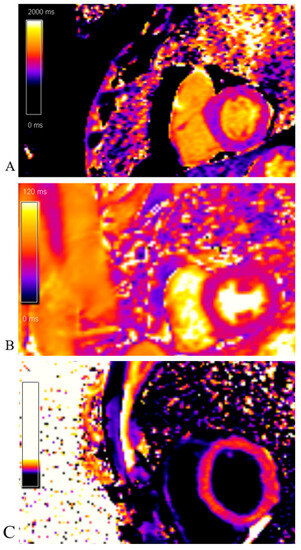

Cardiac magnetic resonance (CMR) imaging performed per protocol showed no visible zones of late pericardial enhancement (LGE) phenomenon (Figure 14).

Figure 14.

Cardiac magnetic resonance imaging: (A) LGE PSIR sequence, short axis, basal view; without visible zones of LGE phenomenon; (B) LGE PSIR sequence, short axis, mid chamber view; without visible zones of LGE phenomenon; (C) LGE PSIR sequence, short axis, apical view; without visible zones of LGE phenomenon.

The native T1 mapping sequence was without areas of prolonged native T1 time (edema/fibrosis). The post-contrast T1 mapping sequence was without areas of shortened post-contrast T1 time (fibrosis) as well (Figure 15).

Figure 15.

Cardiac magnetic resonance imaging: (A)Native T1 mapping sequence; without areas of prolonged native T1 time (edema/fibrosis); (B) T2 mapping sequence; without areas of prolonged T2 time (edema); (C) Post-contrast T1 mapping sequence; without areas of shortened post-contrast T1 time (fibrosis).

CMR is useful for differential diagnoses. Typically, patients with stress cardiomyopathy do not present significant late enhancement, while subendocardial late enhancement is common in myocardial infarction, and focal or subepicardial late enhancement is frequent in myocarditis [18]. Our patient did not exhibit any late enhancement.